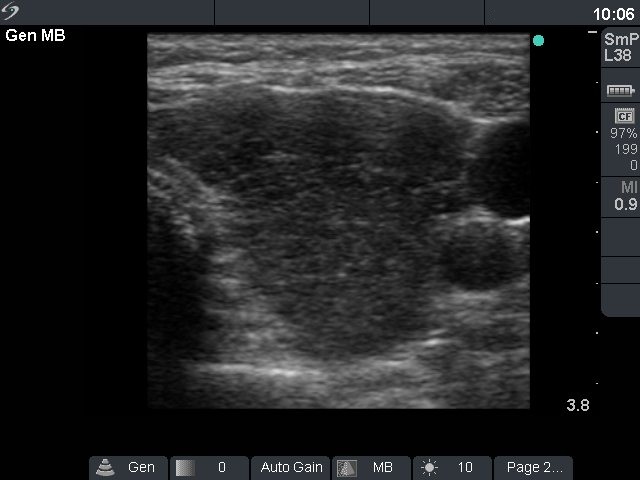

First examination (first row of ultrasound images)

Ultrasonography: the thyroid was diffusely hypoechogenic without any nodule. The vascularization was increased.Thyrostatic drug was administered and the patient went on regular follow-up examinations.